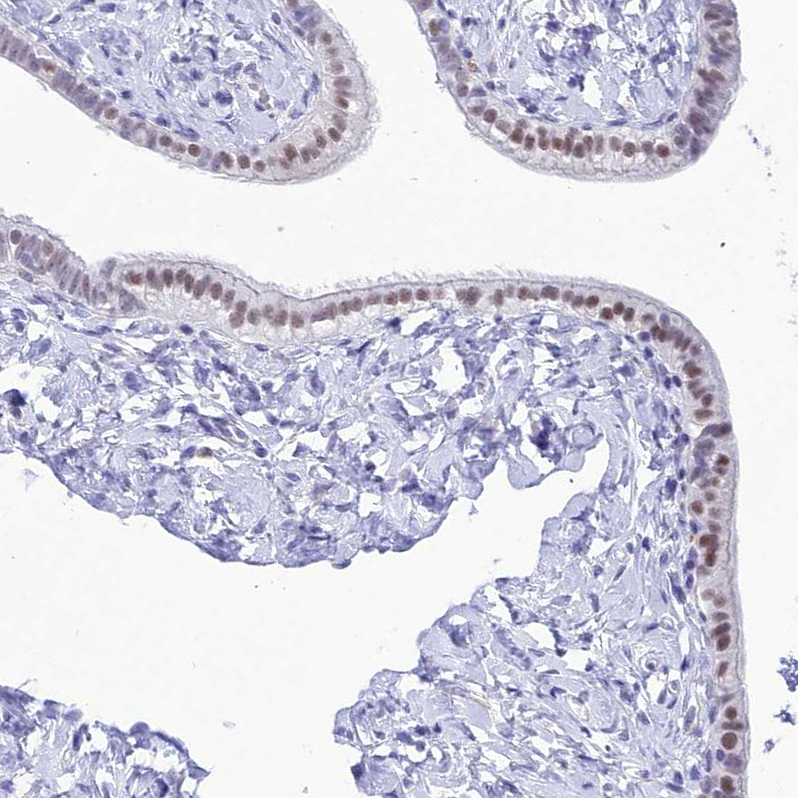

Immunohistochemical staining of human testis shows strong nuclear positivity in Leydig cells, as well as moderate positivity in cells in seminiferous tubules.